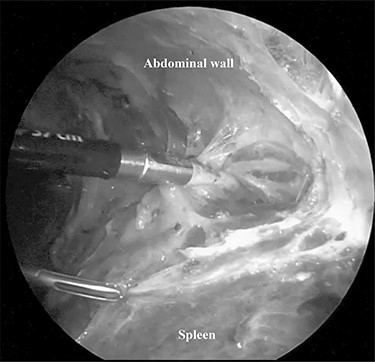

A 79-year-old female patient who had been diagnosed with chronic ITP in September 2014 presented at our hospital. She had received a combined therapy comprising prednisolone and thrombopoietin receptor agonist; however, her platelet count ranged from 0.5 to 59.9 × 104/ul and could not be controlled with oral therapy. Furthermore, she had comorbidities including hypertension, dyslipidemia and diabetes mellitus induced by pre-dnisolone, and a past history of cholecystectomy with an upper abdominal incision. She underwent NS in October 2015, and there were dense adhesions around the spleen supposing to the previous upper abdominal surgery (Fig. 1). The duration of surgery was 163 min and an intra-operative blood loss was 10 ml. Post-operative CT showed a low volume of ascites, which did not require further treatment. She was discharged on the post-operative day 9 with an extremely high her platelet count (135.2 × 104/ul). The weight of the resected specimen was 135 g. Her post-operative platelet count settled at around 45 × 104/ul during 54 months after surgery.

Dense adhesions around the spleen were divided under 3-mm needlescope.

Minimally invasive abdominal surgery performed with needlescopic instruments leads to minimal surgical trauma to the abdominal wall, improved cosmetic result, reduced postoperative pain, lower incidence of wound complication, no risk of port site hernia and earlier recovery. Initially, we used of 2-mm needlescopic instruments for laparoscopic splenectomy (LS); however, the shaft easily bent when manipulating the organs, and there is a high frequency of a butting between the 2-mm needlescope and another forceps due to close proximity to the organs, with a narrow angle of surgical view [2]. Therefore, we utilized 3-mm instruments to overcome the restriction of surgical optics and maneuverability and provide better convenience for the surgeons. However, the risk of tissue damage by the pointed ends of fine graspers or splenosis [3] due to the capsular disruption of the spleen still remains. The dense intra-abdominal adhesions due to previous upper abdominal surgery as seen as Fig. 1 of Case 2 need careful dissection to prevent splenosis. This leads to a longer duration of surgery.